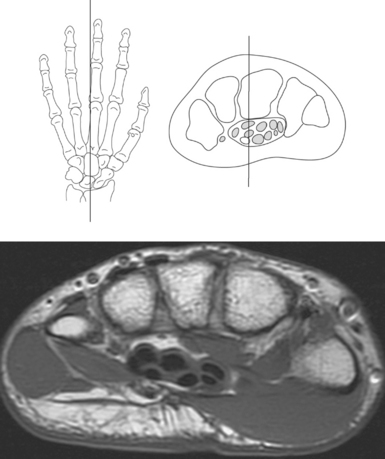

The bony anatomy of the wrist and hand consists of the distal radius and ulna, 8 carpal bones, 5 metacarpals, and 14 phalanges (Figure 9.101). Both the distal radius and ulna have a conical styloid process that acts as an attachment site for ligaments. The radial styloid process is located on the lateral surface of the radius, whereas the ulnar styloid process is located on the posteromedial side of the ulna. The carpal bones are arranged in proximal and distal rows. Located in the proximal row of carpal bones are the scaphoid (navicular), lunate (semilunar), triquetral (triquetrum), and pisiform bones. The pisiform is considered a sesamoid bone that is embedded in the tendon of the flexor carpi ulnaris. The distal row consists of the trapezium (greater multangular), trapezoid (lesser multangular), capitate (os magnum), and hamate (unciform) bones (Figures 9.102 through 9.114). The five metacarpals are small tubular bones with a proximal end (base), distal end (head), and shaft (body). The 14 phalanges that make up the fingers are short tubular bones. Like the metacarpals, each phalanx consists of a proximal (base), middle (body or diaphysis), and distal (head) portion. Each digit consists of 3 phalanges (proximal, middle, and distal), except for the thumb (first digit), which has only 2 phalanges (proximal and distal). The articulation of the phalanges of the second through fifth digits creates three interphalangeal joints: the metacarpophalangeal (MCP) joints classified as condyloid joints, proximal interphalangeal (PIP), and distal interphalangeal (DIP). The proximal and distal interphalangeal joints are classified as hinge joints (Figure 9.101). The first digit, which consists of 2 phalanges, has just two joints: the MCP joint, classified as a saddle joint, and an interphalangeal joint, classified as a hinge joint (Figure 9.101).

The joints of the wrist and hand are quite complex and consist of the following: distal radioulnar articulation, radiocarpal articulation (proximal joint of hand), midcarpal articulation (distal joint of hand), intercarpal articulations (articulations between proximal and distal carpals), carpometacarpal articulations (between carpals and metacarpals), the intermetacarpal articulations (between bases of metacarpals two through five) and the interphalangeal joints (between phalanges of each digit) (Figures 9.111 and 9.115). The distal radioulnar articulation, also called the distal radioulnar joint (DRUJ), is created when the ulnar notch of the radius moves around the articular circumference of the ulna, providing the movements of supination and pronation. The main stabilizing element of the DRUJ is an articular disk called the triangular fibrocartilage complex (TFCC). The TFCC is a fan-shaped band of fibrous tissue that originates on the medial surface of the distal radius and traverses horizontally to insert on the ulnar styloid process (Figures 9.115 and 9.116). It rotates against the distal surface of the ulnar head during pronation and supination and separates the ulna from the carpal bones. The proximal surface of the radiocarpal articulation is formed by the articular carpal surface of the radius and the TFCC, whereas the distal surface is formed by the articular surfaces of the scaphoid, lunate, and triquetrum and the interosseous ligaments connecting them (Figures 9.111 through 9.115). The midcarpal joint is formed by the articulations between the proximal and distal carpal rows (Figures 9.110 and 9.115). The articulation between the carpals within each row creates the intercarpal joints (Figures 9.111 and 9.115). The carpometacarpal joints are formed by the articulations between the carpus and the five metacarpals (Figure 9.111 and 9.115). The carpometacarpal joint of the thumb is an independent joint formed by the articular surfaces of the trapezium and first metacarpal, creating a pure saddle joint. The carpometacarpal articulations of the two to five digits are amphiarthrotic joints with little mobility (Figures 9.105 and 9.115). The intermetacarpal articulation exists between the base of the metacarpals and is joined by the palmar and dorsal metacarpal ligaments (Figure 9.115).

Numerous ligaments provide additional stability to the wrist. The extrinsic ligaments reinforce the joint cavity surrounding the carpal region and include palmar and dorsal radial carpal ligaments, the radial and ulnar collateral ligaments, and the TFCC (Figures 9.115 through 9.117). The many articulations between the carpal bones are supported by the intercarpal ligaments or intrinsic ligaments that connect the carpal bones to each other (Figure 9.115). The configuration of the intrinsic ligaments, metacarpal ligaments, and triangular fibrocartilage complex creates five different joint compartments that can be demonstrated at arthrography: (1) compartment of the first carpometacarpal articulation, (2) common carpometacarpal compartment, (3) mediocarpal compartment, (4) intermetacarpal compartment, and (5) radiocarpal compartment (Figure 9.115). The carpal tunnel is created by the concave arrangement of the carpal bones (Figure 9.103). A thick ligamentous band called the flexor retinaculum (transverse carpal ligament) stretches across the carpal tunnel to create an enclosure for the passage of tendons and the median nerve (Figures 9.118 through 9.120). The flexor retinaculum inserts medially on the pisiform and hook of the hamate and spans the wrist to insert laterally on the scaphoid and trapezium. In addition to the carpal tunnel, another tunnel called Guyon’s canal is formed where the ulnar extension of the flexor retinaculum continues over the pisiform and hamate. This creates a potential site for compression of the ulnar nerve (Figures 9.118, top, and 9.119). The extensor retinaculum (dorsal carpal ligament), located dorsally, is much thinner. It attaches medially to the ulnar styloid process, triquetrum, and pisiform and laterally to the lateral margin of the radius (Figure 9.120, left). Along its course it forms six fibroosseous tunnels for the passage of the synovial sheaths containing the extensor tendons (Figure 9.118, bottom).